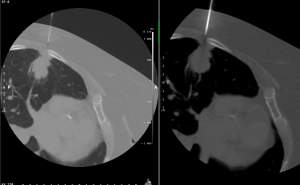

Perkutánní biopsie a drenáž tekutinové kolekce pod kontrolou CT

Perkutánní biopsie (drenáž) pod kontrolou CT (počítačové tomografie) je definována jako cílené umístění speciální bioptické jehly nebo drénu do chorobného ložiska za účelem odběru tkáně, buněk či tekutiny pro další šetření.

Perkutánní biopsie je diagnostický výkon – odběr vzorku tkáně z chorobného ložiska. Je nutná pro přesnější určení povahy chorobného procesu, ze kterého byl vzorek odebrán, je nutná pro stanovení dalších léčebných postupů. Často rozhodne, zda-li se jedná o zhoubný či nezhoubný proces a umožní usměrnit další léčení.

Perkutánní drenáž je zavedení tenké trubice (drénu) do kolekce tekutiny v těle. Jedná se o výkon léčebný i diagnostický. Dutina s tekutinou je při drenáži vypuštěna, odebraná tekutina je odeslána k rozboru.

Co se vlastně při biopsii odehrává?

Na vyšetřovně, kde se bude výkon provádět je pacient uložen do polohy umožňující nejlepší přístup k ložisku. V této poloze musí po dobu výkonu pokud možno bez pohybu setrvat. Lékař provádějící výkon zaměří přístrojem ložisko, určí nejbezpečnější přístup, provede místní znecitlivění místa vpichu, zavede bioptickou jehlu, provede odběr vzorků. Poté jehlu odstraní a místo vpichu převáže.

V případě zavedení drénu k lepší a trvalejší evakuaci tekutého obsahu ložiska se drén většinou po fixaci ke kůži ponechá k dalšímu ošetřování na oddělení nemocnice.

Protože se výkon provádí s lokálním umrtvením místa vpichu jehly, je většinou dobře snesitelný. Nepříjemné bývá pouze samotné zavedení bioptické jehly do ložiska, jedná se však o krátkodobý diskomfort. Trvání výkonu je značně individuální v závislosti na uložení ložiska a jeho vztahu k okolním strukturám, odhad času Vám upřesní lékař, který bude výkon provádět. Po výkonu je pacient odvezen zpět na lůžkové oddělení, kde setrvá zpravidla 1–2 dny.